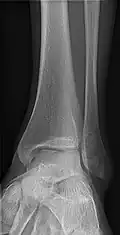

Extremities

A projectional radiograph of an extremity confers an effective dose of approximately 0.001 mSv, comparable to a background radiation equivalent time of 3 hours.[16]

• Tibia and Fibula - AP and Lateral

• Ankle - AP/Mortice and Lateral